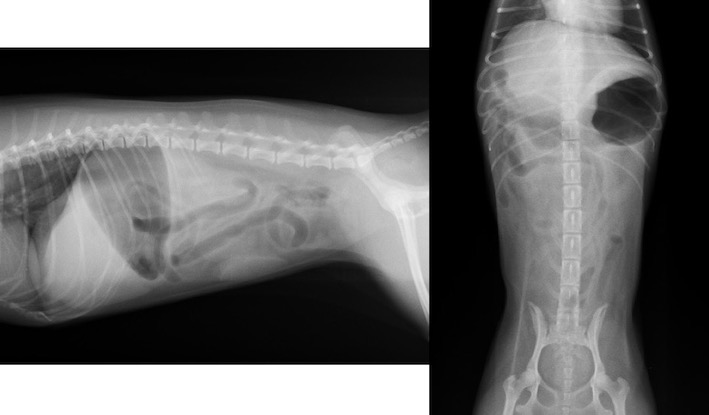

レントゲン検査画像です。